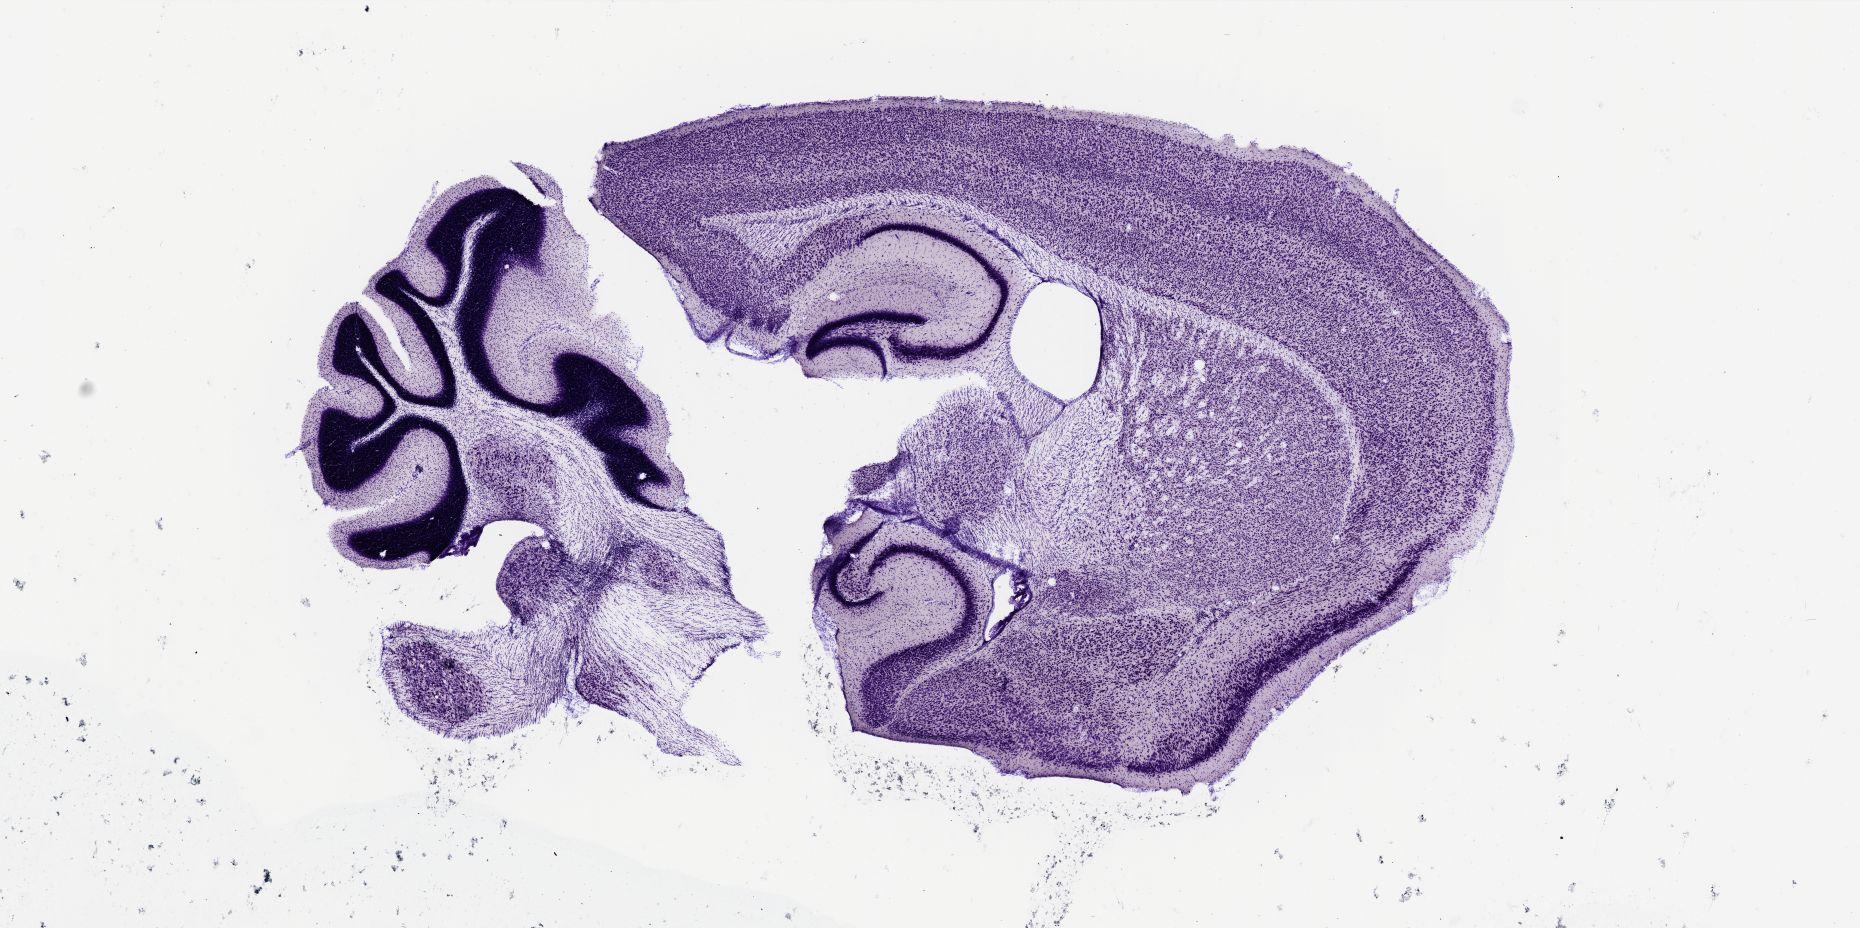

Datasets -> Mus Musculus -> Nissl, sagittal, histo, Whole-Brain, adult

[ Metadata ]   ·   Source: Shawn Mikula

thumbnail

m07a